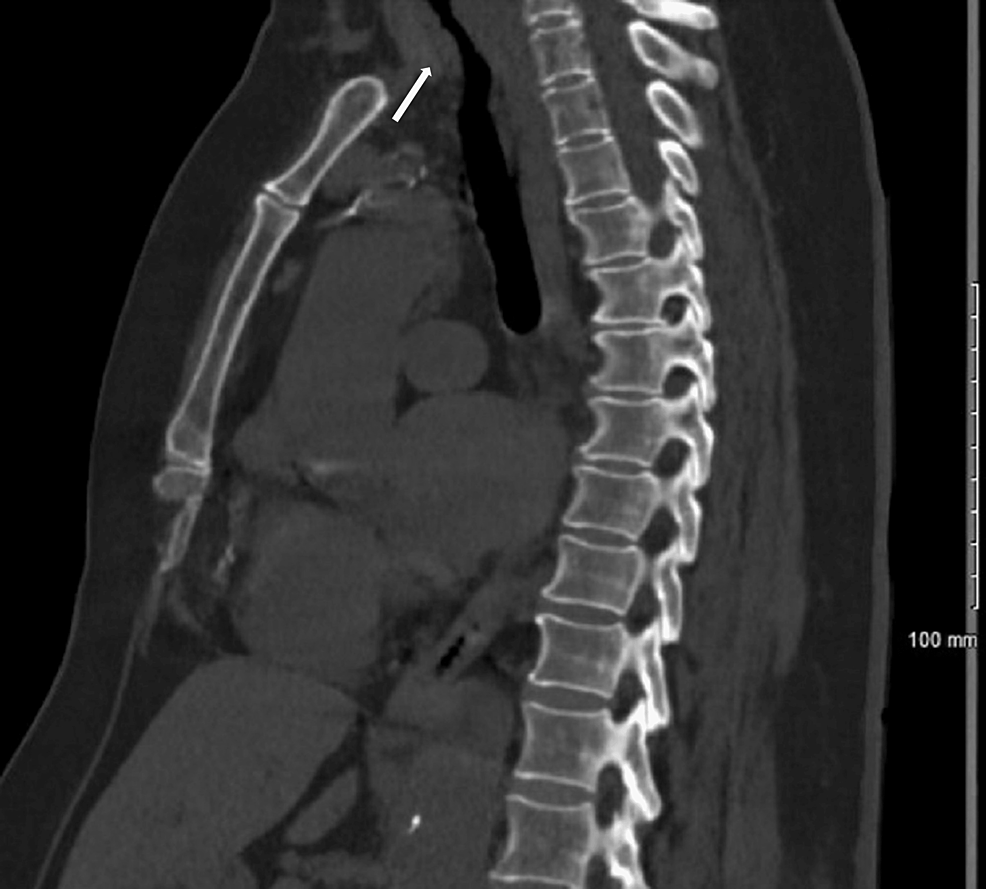

From www.globalradiologycme.com

Post Intubation Tracheal Stenosis Tracheal Stenosis Following Endotracheal Intubation Tracheal stenosis following prolonged intubation is a relatively rare but serious problem. Although infraglottic stenosis most commonly results from endotracheal tube damage, it may occur after damage of the 1st tracheal ring or. Tracheal stenosis is a common complication of endotracheal intubation or tracheostomy, resulting in significant morbidity. Nonmalignant tracheal stenosis is a potentially life threatening conditions that develops as. Tracheal Stenosis Following Endotracheal Intubation.